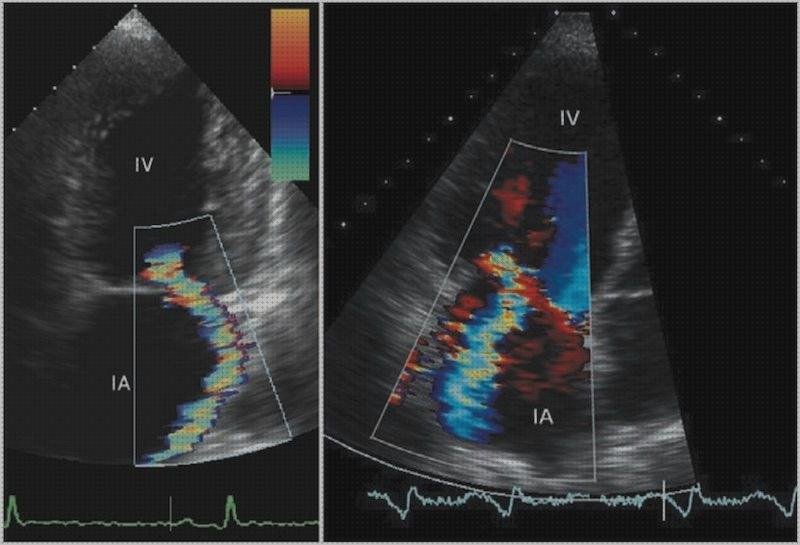

La ecografía permite también analizar la forma y el funcionamiento de las válvulas del corazón (válvulas mitral, aórtica, tricúspide y torácico). La ecocardiografía “doppler color ”, “doppler pulsado ” y “doppler progresivo ” son técnicas particulares que se usan de práctica al realizar una ecografía del corazón, y que nos presentan cómo se desplaza la sangre dentro de las cavidades cardíacas.

El ecocardiograma doppler color, doppler pulsado y doppler continuo nos dejan estudiar las anomalías en la circulación de la sangre dentro del corazón, provocadas habitualmente porque una o múltiples válvulas están enfermas. El ecocardiograma puede advertir con facilidad la estenosis y/o la insuficiencia de las válvulas cardíacas, así como otras variaciones más sofisticadas de su funcionamiento. Tanto las estrechamiento como las insuficiencias valvulares pueden provocar insuficiencia cardiaca.